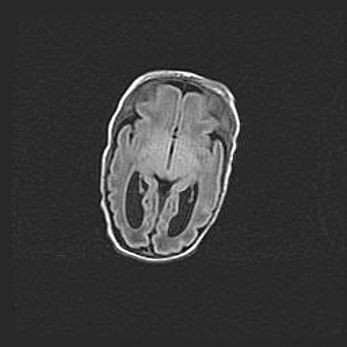

Лейкомаляция с кистозно-глиозной дегенерацией головного мозга.

Возраст: 2 месяца 25 дней

Вес: 6400 г

Окружность головы: 40 см

Срок гестации: 41 неделя

Лейкомаляцию относят к ишемически-гипоксическим повреждениям головного мозга, диагностируемым у новорожденных. При лейкомаляции в головном мозге обнаруживают очаги некроза, возникшие после тяжелой гипоксии и нарушения кровотока. В процессе морфогенеза очаги проходят три стадии: 1) развития некроза, 2) резорбции и 3) формирования глиозного рубца или кисты. Перивентрикулярная лейкомаляция (ПЛ) встречается примерно в 12% случаев среди новорожденных, обычно – у недоношенных детей, причем, частота ее зависит от массы, с которой младенец появился на свет. Наибольшее число малышей страдает лейкомаляцией, если масса при рождении 1500-2500 г.